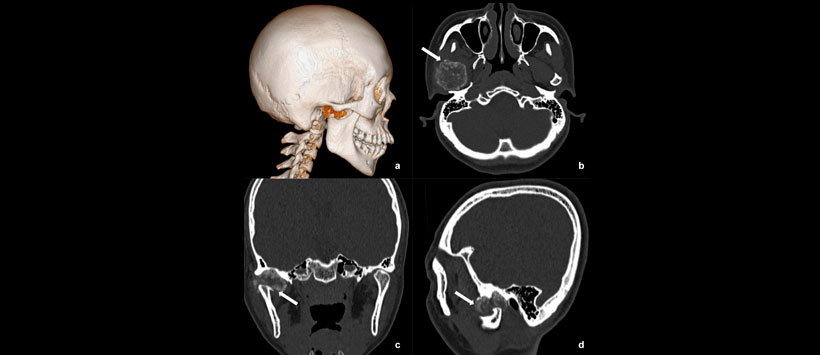

Figura 5: Tomografía Computarizada (TC) en la que se detectó una masa heterogénea (flechas blancas) alrededor del cóndilo mostrado en la reconstrucción tridimensional (a), horizontal (b), coronal (c) y sagital (d)